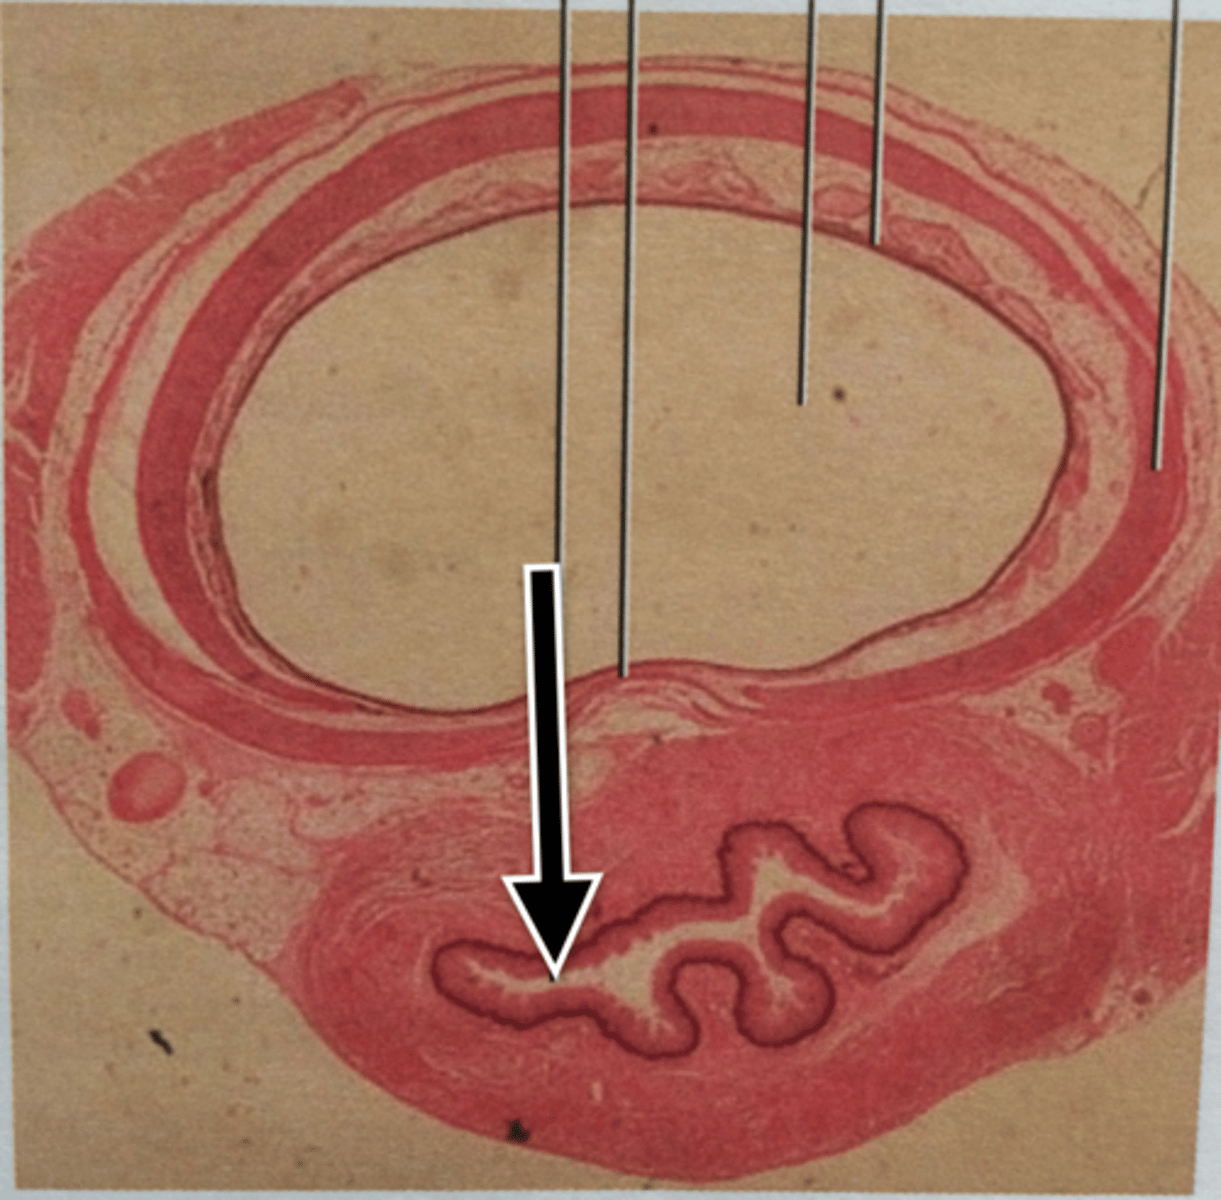

Epithelial Lining of Trachea

Lumen of Esophagus

Lumen of Trachea